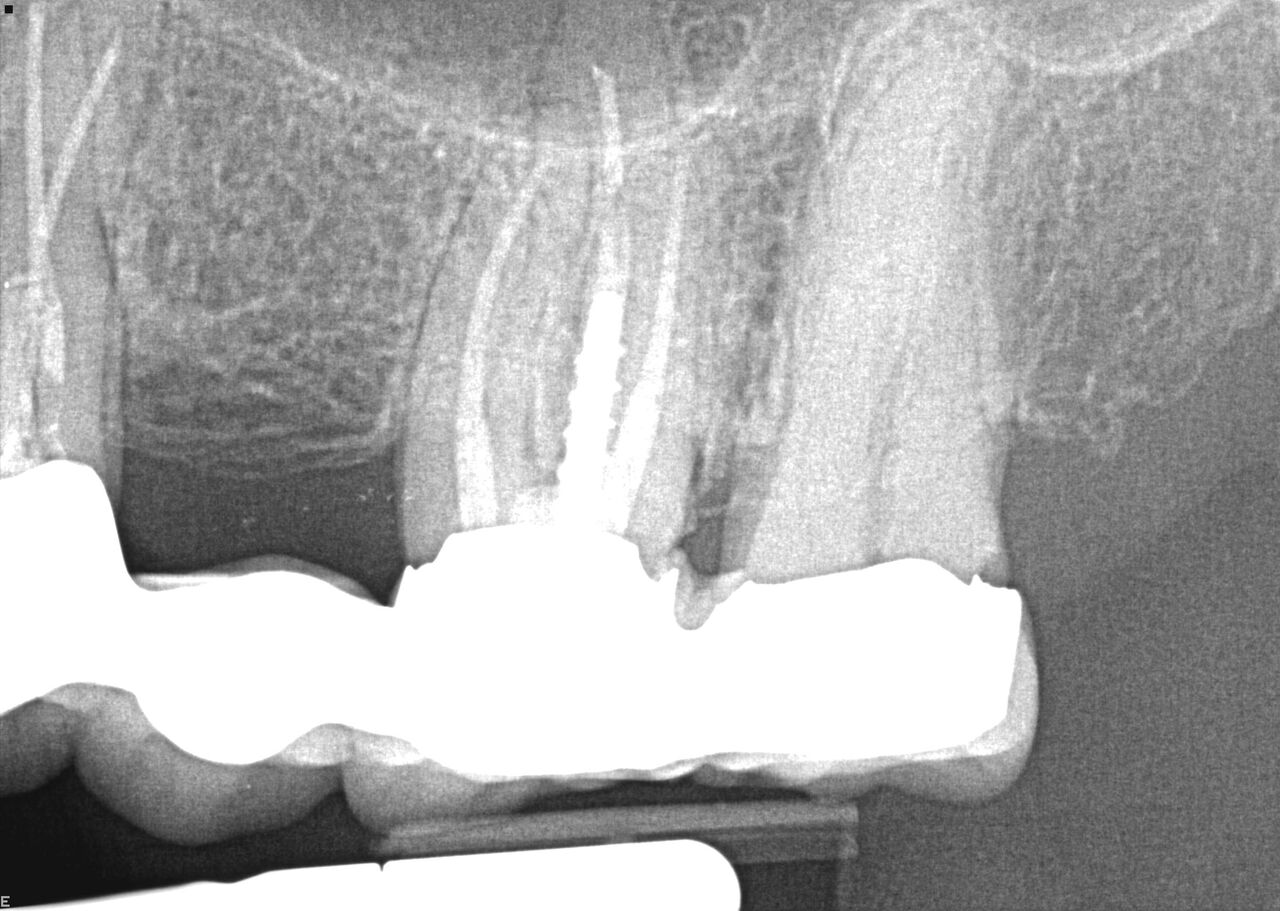

(1.) Case 1 initial radiograph of No. 19.

Figure 1

A 63-year-old woman presented with severe pain on biting of tooth No. 19 (Figure 1). Clinically there was pain on percussion and significant periodontal probing along the mesial root. The patient was anesthetized with infiltration anesthesia and the crown was horizontally sectioned from the lingual of the tooth. The remaining tooth was sectioned so the roots could be extracted individually. The socket was fully debrided and an implant was placed (Figure 2), which was prosthetically correct and stabilized in excess of 45 Ncm. The bone was milled to allow for unimpeded placement of a temporization abutment. The initial crown was revised to be the temporary crown in infraocclusion. Cement was extruded extraorally (Figure 3) prior to seating of the temporary restoration. The socket was sealed with the temporary crown and there were no sutures or bone graft (Figure 4 and Figure 5).